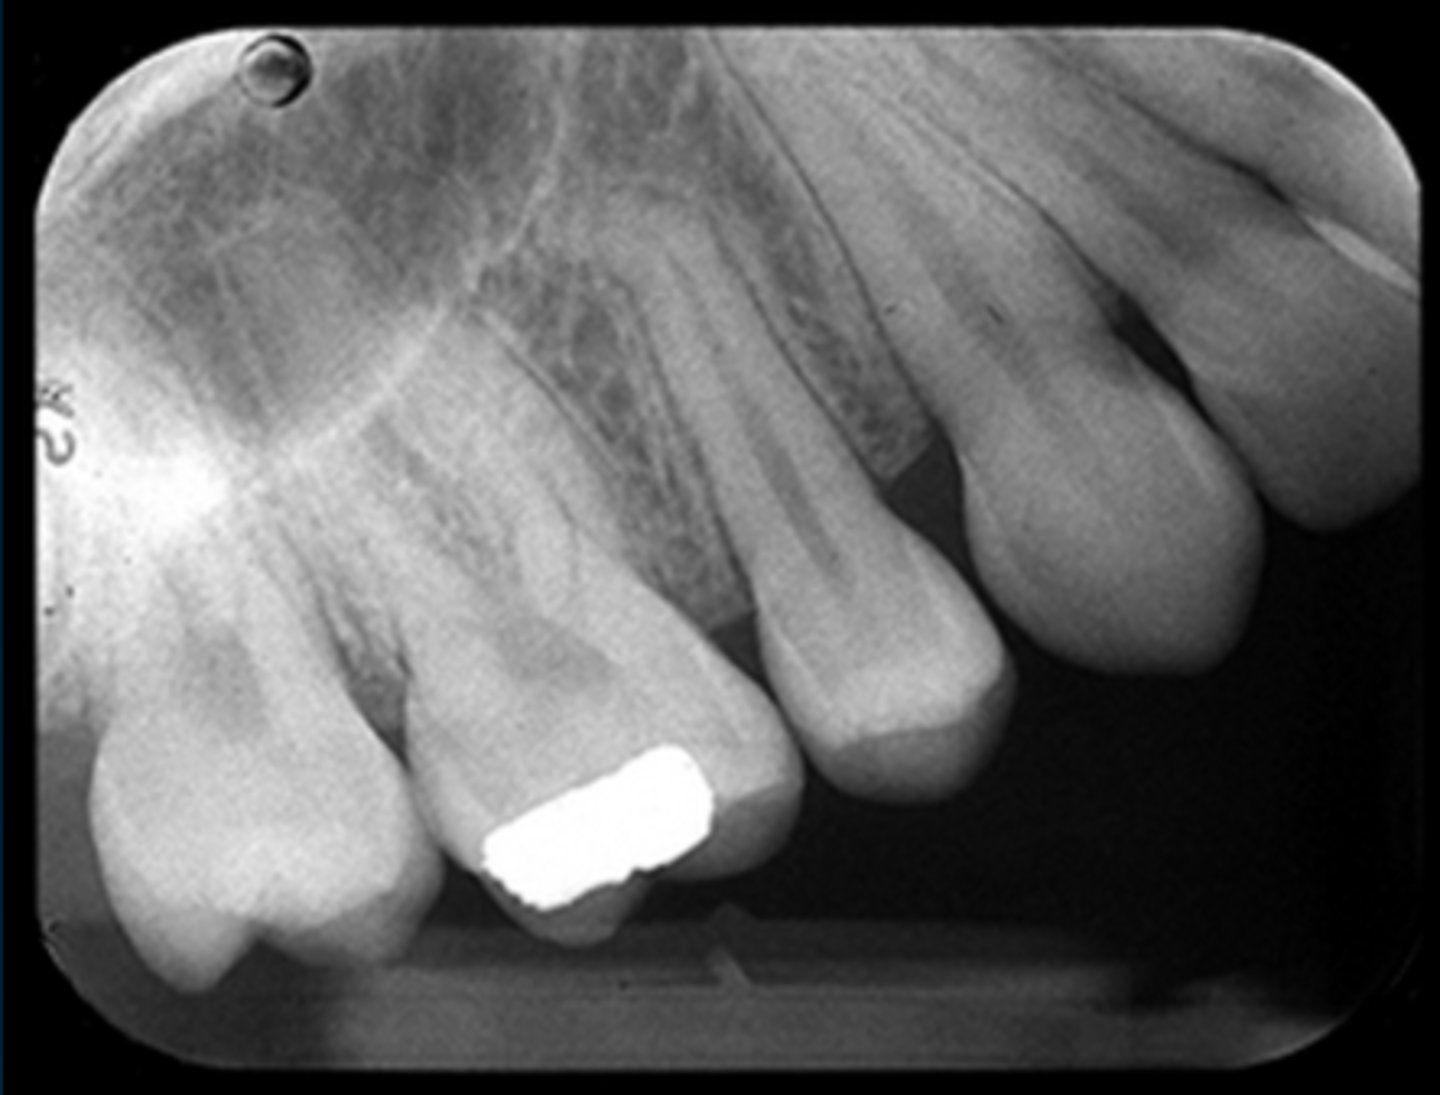

Apical cut-off